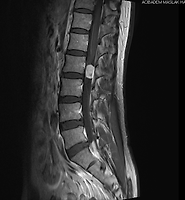

| [척추종양] 증상, 진단에서 수술 후기 (57) | 2014.03.25 |